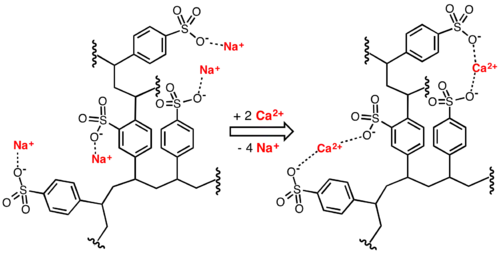

Mechanism of action

Hyperkalemia

Polystyrene sulfonates release sodium or calcium ions in the stomach in exchange for hydrogen ions. When the resin reaches the large intestine the hydrogen ions are exchanged for free potassium ions, and the resin is then eliminated in the feces. The net effect is lowering the amount of potassium available for absorption into the blood and increasing the amount that is excreted via the feces. The effect is a reduction of potassium levels in the body, at a capacity of 1 mEq of potassium exchanged per 1 g of resin.[8][11]

Polystyrene sulfonates are useful because of their ion exchange properties.[15] Linear ionic polymers are generally water-soluble, whereas cross-linked materials (called resins) do not dissolve in water. These polymers are classified as polysalts and ionomers.[15]

Water softening

Water softening is achieved by percolating hard water through a bed of the sodium form of cross-linked polystyrene sulfonate. The hard ions such as calcium (Ca2+) and magnesium (Mg2+) adhere to the sulfonate groups, displacing sodium ions. The resulting solution of sodium ions is softened.